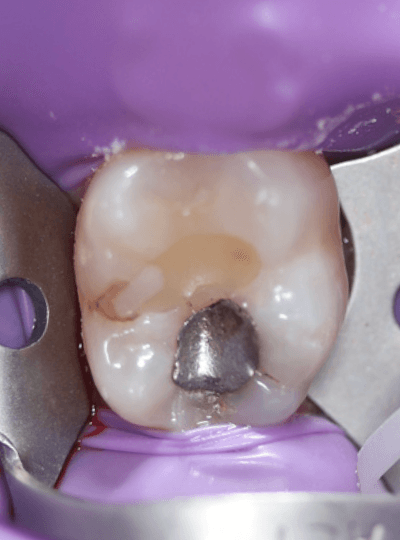

Isolation

As there was no marginal ridge loss, single tooth rubber dam isolation was sufficient. Usually I do multiple teeth to aid visualisation and access for proximal regions. I like using winged clamps where I place the rubber dam sheet and clamp all in one go, but more recently I’ve been placing wingless clamps followed by the rubber dam sheet.